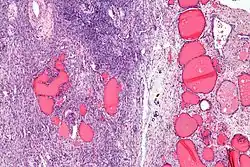

| Micrograph of a struma ovarii. Characteristic thyroid follicles are seen on the right, and ovarian stroma on the left. H&E stain. | |

A struma ovarii (literally: goitre of the ovary) is a rare form of monodermal teratoma that contains mostly thyroid tissue, which may cause hyperthyroidism.[1]